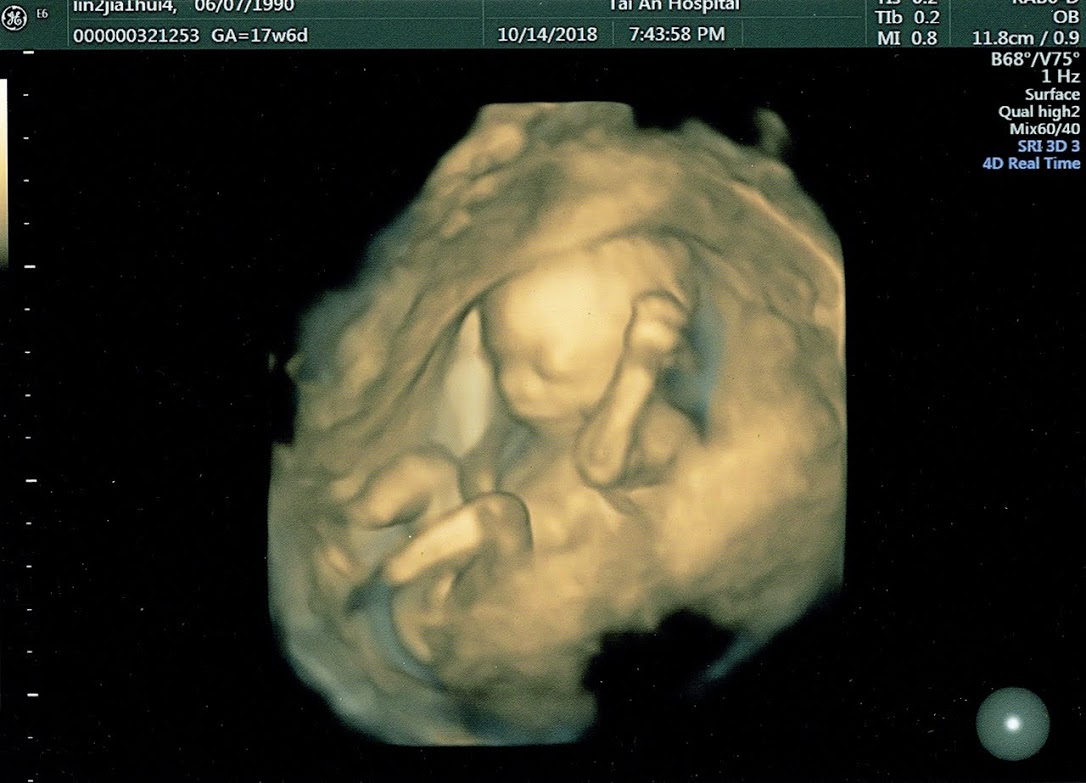

今晚終於要去〈臺安進化總院〉照【3D立體超音波】照相??? 由於懷孕才17週又6天,所以基本上這次只是去醫院照個寶寶整體姿勢當作留念,反正是院方贈送的啦!!!(超過18週就不能使用了!!自費是880元/張)?? 剛開始檢驗人員只照到縮成一團的寶寶,後來換個角度照,就照到了他的生殖器官???,她還指了螢幕上那兩個橢圓形給我們看?? 隨著檢驗人員的操作,寶寶也開始從縮成一團轉變成伸展筋骨,讓我們順利地完成這次的【3D立體超音波】照相!? 最後我們選了寶寶貌似微笑的面容當作留念??? 我覺得寶寶的眼睛應該像我,因為我閉眼睛時眼窩也很大!!?? 不過不管是3D或者是4D的立體超音波,畫面中所產生的影像都是由機器程式所組成的模樣,所以都只是模擬寶寶出生後的模樣,通常只能當參考用?

總之呢,我之後就要去做高層次超音波了,希望寶寶能像模擬照片中那般健康活潑?